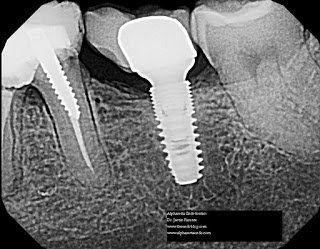

This patient presented with a history of root canal treatment on #20 by an endodontist 1-2 years ago. #19 was treated by her general dentist ~8 months ago, and #18 was fractured and replaced with an implant within the last two years. The crown came loose and was replaced with a post 1 month ago. Following this treatment, she described severe pain upon chewing and swelling on her tongue side of the tooth. There is no extraoral sign of swelling or lymphadenapathy. No intraoral swelling or sinus tract. Around #19, the gingiva is edematous and inflamed with bleeding on probing. The crown margins are open and overextended. The probing depths on #19 are 3 mm interproximally and 8-9mm mid buccal and mid lingual. The radiograph reveals a laterally widened PDL with a hint of an apical radiolucency. The restoration on the mesial is into the furcation and associated with horizontal bone loss. #20 displays an apical radiolucency as well. The implant on #18 is bulbous and overcontoured to the mesial with some signs of horizontal bone loss.

Unfortunately, I recommended extraction of #19 due to the likelihood of a vertical root fracture and a poor restorative prognosis. I recommended she return to her previous endodontist for reevaluation/recall of #20. I also provided her some proxibrushes to maintain oral hygiene around #18. Would you rather have that root canal/crown or that implant…or neither?